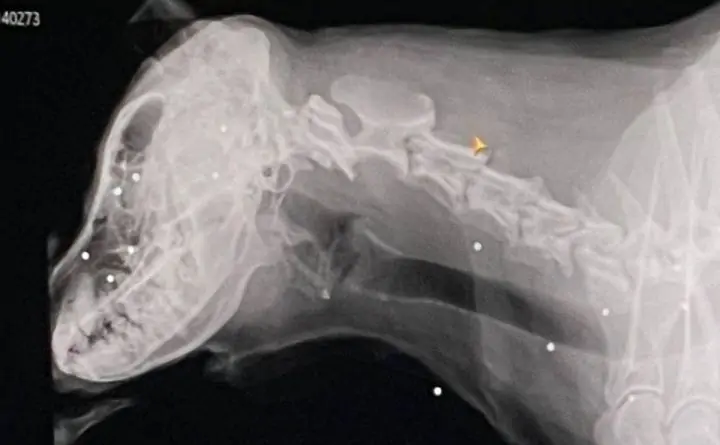

Собака пропала ещё 17 декабря и хозяева начали поиски. Пса нашли спустя неделю всего в крови. В ветеринарной клиники хозяевам сообщили, что две дробин застряли возле глаз, ещё несколько — у трахеи, а остальные — в голове и правой лапе.

Предварительно, неизвестные стреляли в собаку издалека. Ей предстоит долгое восстановление.